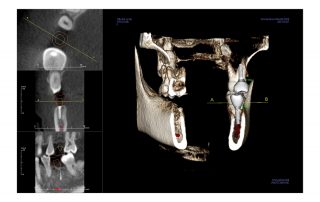

i-CAT FLX V8

The V8 represents your gateway into the world of industry-leading 3D CBCT imaging at an affordable price. With 8cm x 5cm and 8cm x 8cm FOVs, this system accommodates those clinicians who want to capture select treatment areas for survey – implant, oral surgery and endodontic.